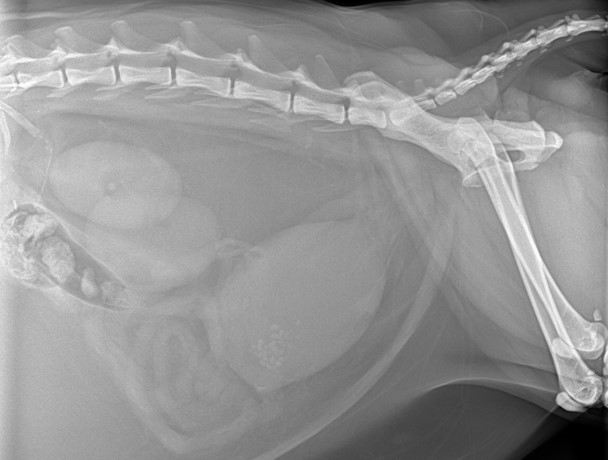

當膀胱環境受到發炎感染或是飲食的刺激與改變,就可能導致結石的產生,結石在膀胱裡面翻滾會使膀胱黏膜受損,進一步惡化發炎,甚至小石子不小心滾到尿道,就會造成尿路阻塞!一但當醫生診斷出尿路完全阻塞,就需要做麻醉導尿的動作,先把堆積的尿尿先排出,導尿管一般來說需要放置3-5天,配合留院觀察與輸液治療,讓發炎的膀胱慢慢復原,等狀況穩定後移除導尿管,觀察到正常排尿才能出院。結石的處理方法有分外科移除或是內科食療,這與結石的種類還有每隻貓咪的狀況而有所不同,需要專業的醫師做評估並給予治療建議。以上三個問題,都會直接或間接的造成膀胱本體發炎,發炎的情況下,容易產生一些細胞碎屑或組織,一個不小心,就有可能塞住尿道,若是部分塞住,就像水管卡了一些髒髒的東西,尿的不順,主人會發現貓咪一直進出貓砂盆,每次都只有一點點;若是完全塞住,尿液排不出去往膀胱堆積,膀胱就會越撐越大,身體的代謝廢物無法從尿液中排出,又被重新吸收回體內,這就是尿毒症,尿毒症一但發生,貓咪就會出現虛弱無力、厭食、嘔吐等症狀。而代謝廢物中最可怕的就是鉀離子,鉀離子正常會透過尿液排出,如果塞住了排不出去,就會導致血中鉀離子濃度上升,也就是高血鉀,當血鉀太高時,心臟就會停止跳動了!所以,完全尿不出來是急診,需要趕緊就醫,超過24小時沒有排尿,導致死亡風險也隨之上升。另外,尿路阻塞是有可能會復發的!不是導完尿就沒事了,需要針對導致阻塞的原因去做治療與預防。

▲ 尿路阻塞膀胱變大,X光可見膀胱結石。